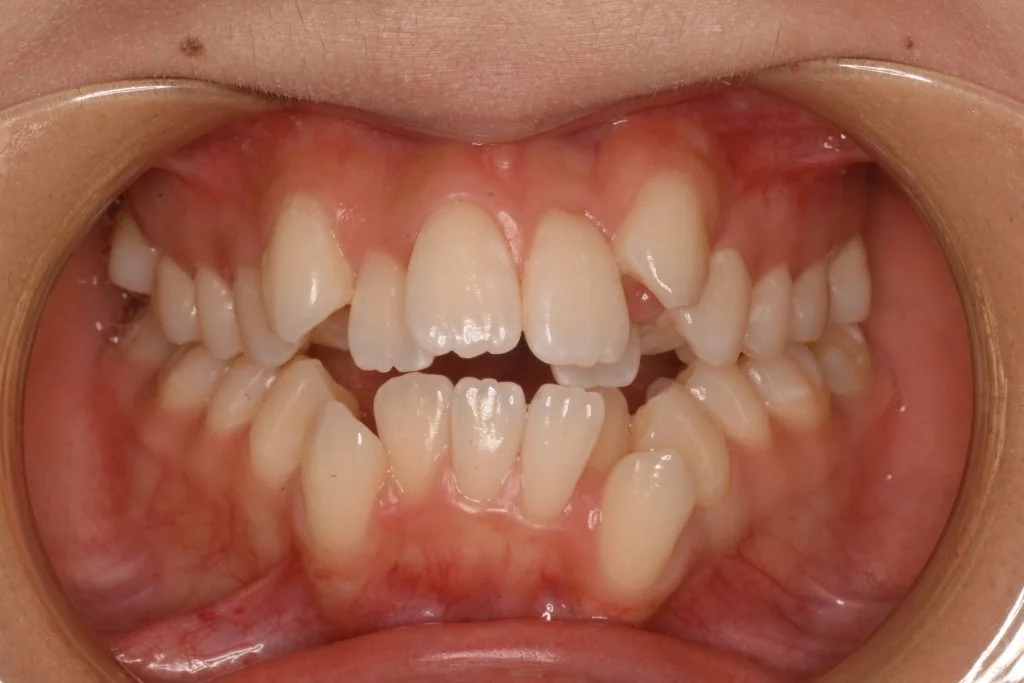

• 症例1-1治療前

治療前

患者さんのお悩み、希望 八重歯、ガタガタがひどくて人前で笑えない。笑うときは手で隠して笑うのが癖になっているので、歯並びを治して人前で気にせず笑えるようになりたい。ただ口内炎ができやすいので、ワイヤー矯正ではなくマウスピースで治療したい。何件か相談にいったが、どこの病院でもワイヤー矯正じゃないと難しいと言われ諦めかけている。

治療方法 上下4本抜歯のマウスピース矯正(インビザライン)

治療期間 1年10ヶ月